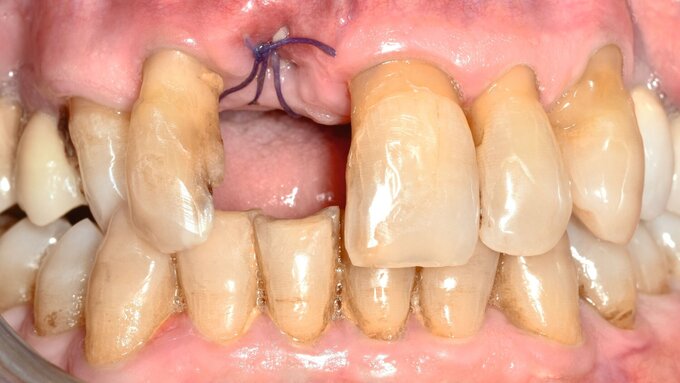

Grundsätzlich sind alle zahnärztlichen Therapieoptionen bei pflegebedürftigen, geriatrischen Patienten genauso anzuwenden wie bei gesunden Erwachsenen. In der mobilen Zahnmedizin existieren allerdings folgende Besonderheiten, die den Reparaturvorgang maßgeblich beeinflussen können:

Faktor Zeit, kurze Behandlungsintervalle

Dysphagie, gegebenenfalls mit Würgereiz und unkontrolliertem Schlucken

Tremor

Erschwerte Trockenhaltung

Ungünstige Sicht bei aufrechter Lagerung und gebeugter Arbeitshaltung

Reduzierte Materialauswahl

Anhand der in Abbildung 1 dargestellten Standardarbeitsabläufe bei der Reparatur unterschiedlicher Werkstoffoberflächen mit Komposit müssen für die mobile Zahnmedizin geeignete Materialien und in der aufsuchenden Betreuung einsetzbare technische Hilfsmittel definiert werden. Nur in sehr seltenen Fällen ist ein Wasser-Pulverstrahlgerät bei der aufsuchenden Betreuung verfügbar. Es sollte daher eine mikroretentive Oberfläche mit Alternativen wie Soflex-Scheiben, Finierstreifen oder Diamanten geschaffen werden. Hinsichtlich der Adhäsivtechnik werden die seit geraumer Zeit verfügbaren Universaladhäsive bereits von vielen Praxen verwendet und bieten bei der Reparatur aufgrund ihrer vielseitigen Anwendbarkeit im self-etch-, selective-etch- und total-etch-Modus deutliche Vorteile gegenüber Adhäsiven der früheren Generationen [Kanzow et al., 2019; Rosa et al., 2015]. Möglicherweise könnte die zusätzliche Verwendung eines Silans zur Erhöhung der Haftkraft auch beim Universaladhäsiv im klinischen Standardvorgehen vorteilhaft sein [Stape et al., 2022], für das Reparatur-Protokoll in der mobilen Zahnmedizin wird dies zunächst jedoch nicht berücksichtigt.

Bei der Adhäsivtechnik in der mobilen Zahnmedizin kann es sinnvoll sein, das Total-etching aufgrund des zusätzlich reinigenden Effekts der Phosphorsäure auf zahlreichen Werkstoffoberflächen zu bevorzugen. Hauptgrund hierfür ist, dass eine adäquate Trockenlegung in der Regel nur erschwert erfolgen kann und mit Kontaminationen durch Speichel und Blut im Behandlungsvorgang gerechnet werden muss. Als mögliche Materialien für eine intraorale Reparatur werden modifizierte Glasionomerzemente, Komposite, Bulk-Fill-Komposite, Flow Komposite (bei Klasse V) sowie dualhärtende Komposite genutzt. Für die dualhärtenden Komposite ist allerdings darauf hinzuweisen, dass herstellerabhängig überprüft werden sollte, ob diese mit einem self-etch-Adhäsiv kombinierbar sind. Gegebenenfalls sollte bei dualhärtenden Kompositen das jeweilige vom Hersteller empfohlene Adhäsivsystem verwendet werden, um Einbußen in der Haftkraft zu vermeiden.